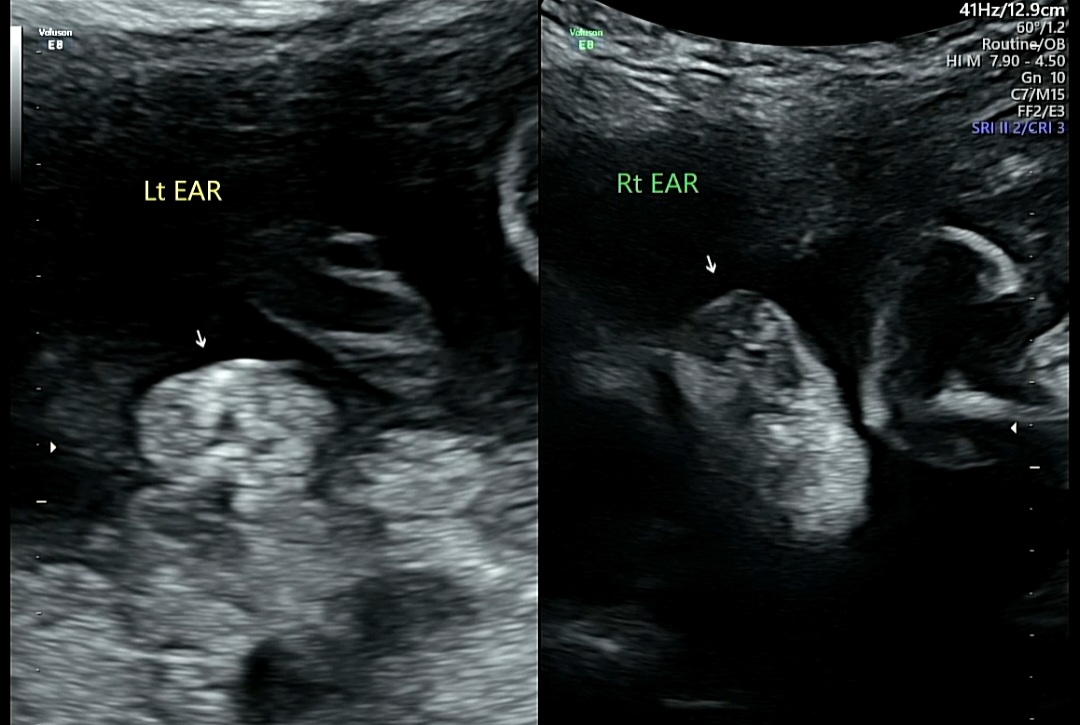

7. 얼굴 발달 확인

2) LT EAR(왼쪽 귀)/RT EAR(오른쪽 귀)